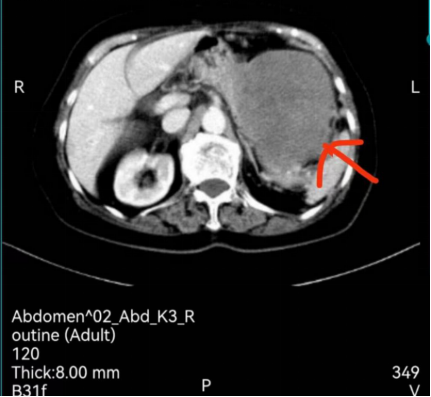

宋奶奶今年已82岁高龄,于2023年3月2日入住江西省人民医院(南昌医学院第一附属医院)肝胆外科。入院诊断为腹腔肿瘤、腹腔粘连、肝囊肿、单纯性肾囊肿、残胃炎及肺部阴影。她有过三次手术史,分别是胃切除术、胃结石取出术、胆囊切除术,由于食欲不振,精神萎靡,年纪大不肯去医院治疗。家属带她去体验时发现腹腔内有肿瘤,肿瘤位于腹膜后,直径达15cm,毗邻胰腺和脾脏,向上压迫胃,与脾血管、右侧肾血管关系紧密,手术难度非常大且复杂。

家属考虑患者年纪大、家庭经济状况不佳,犹豫不决,一度想放弃手术。徐志丹向患者家属详细了解病史及家庭状况,组织邀请肿瘤科、CT室、麻醉科、神经内科、泌尿外科、胃肠外科MDT会诊。完善各项检查,准备充分后于3月14日在全麻下行开腹控查术+腹膜后肿瘤切除术+脾切除术+大网膜清扫+肠粘连松解术,术中发现网膜及肠道与腹壁广泛粘连,肿块表面与网膜及肠道粘连致密,肿块下级与脾动静脉粘连紧密。徐志丹团队用精湛的技术完成手术,手术历时4小时,出血仅100ml。术后患者生命体征平稳,在护士长付文兰带领的护理团队精心护理下恢复良好,3月27日康复出院。